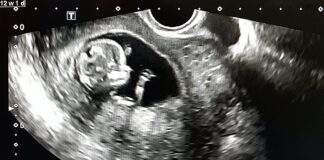

Tag: trimester